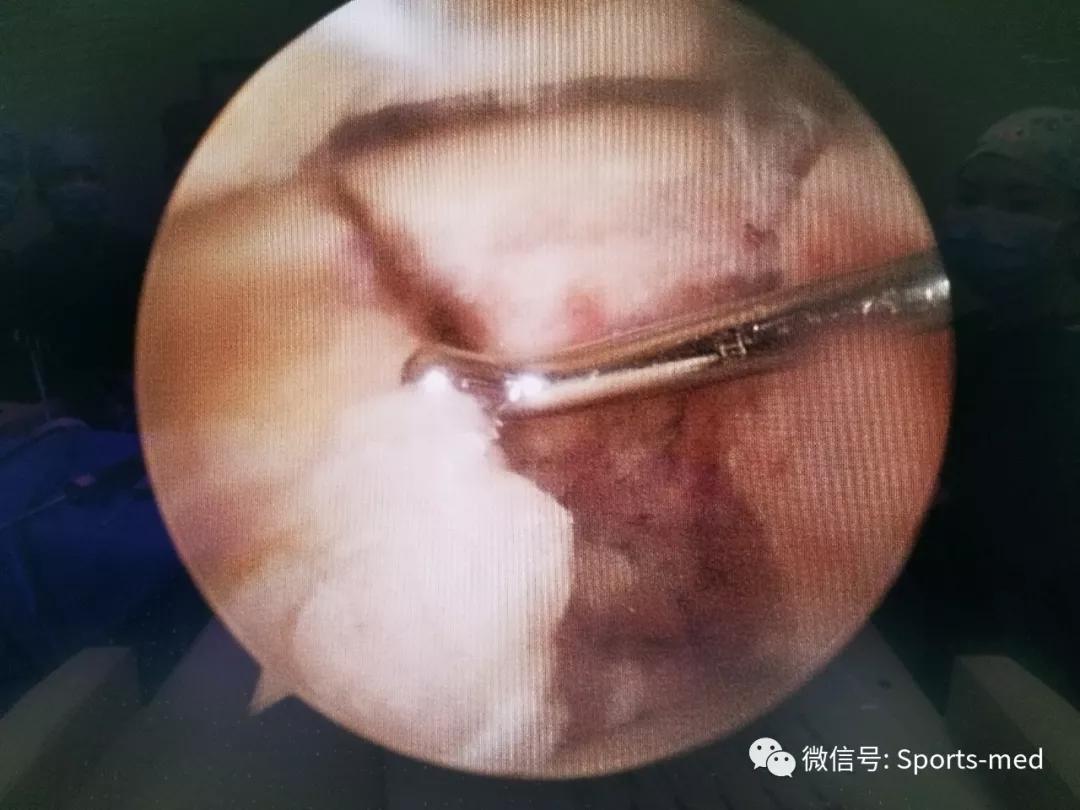

我们采用常规的后内、后外入路,清理关节内的淤血,并探查骨折情况,与ct显示基本一致,骨折形成三部分,并累积了关节面

经过我们反复敲拨以及结合克氏针的使用,我们首先 把上方的骨块和外侧的骨块复位,打上三枚克氏针固定,然后打入两枚空心埋头钉,复位的效果还是相当满意,骨折线基本看不到了

然后再清理一下距下关节,把影响另一块骨块复位的组织清理掉,还需要额外松解一下这个骨块上的纤维组织,尤其是这个骨块与拇长屈肌腱腱沟以及相应的支持带有关联,这些组织的牵拉影响了骨块复位,所以我们对这些支持带做了松解,同时不影响拇长屈肌腱,松解后复位容易多了,复位后再打入另外两个埋头钉,效果就变成这样了:

距下关节的复位也非常满意啦,可以做到了解剖复位,而且只是通过关节镜的两个0.5公分的小切口完成了这个手术,手术时间1.5小时,患者发生血管神经损伤以及距骨坏死的机率应该已经尽最大强度在降低了,希望患者能够早日康复,我们也希望能够继续追踪随访患者,以获取更多的经验,提高此类型损伤的治疗效果和水平,最后展示一张我们的照片吧